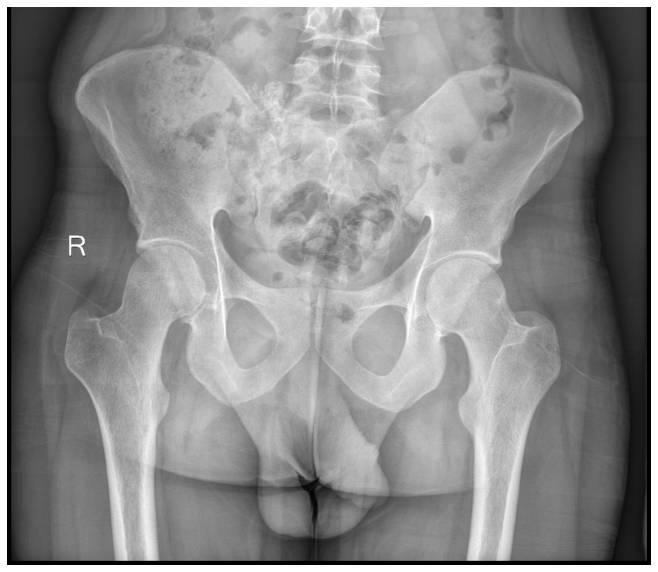

Ameliyat Öncesi: Röntgende sağ sakroiliak bölgede düzensizlik ve ossifikasyon görülmekte